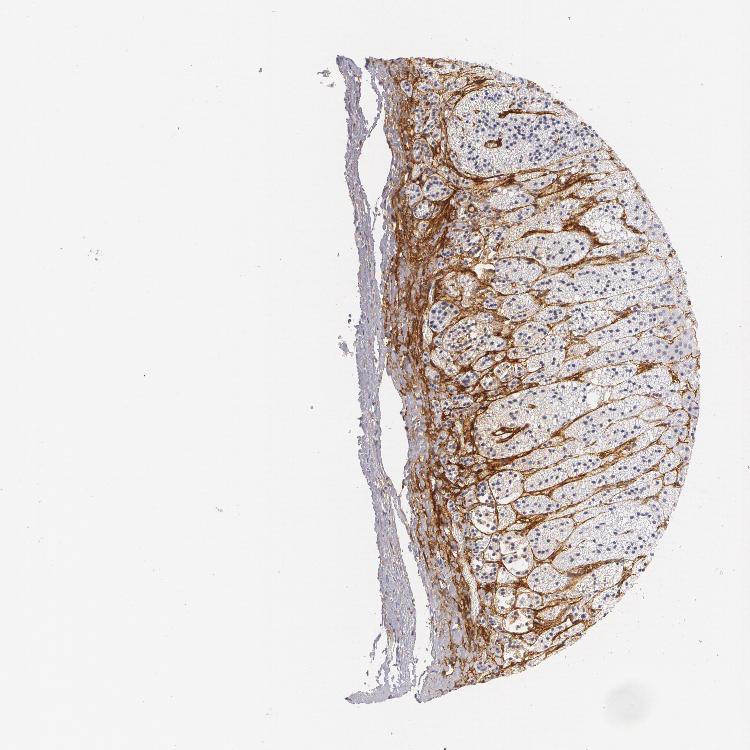

ADRENAL GLAND - Antibody stainingi

Antibody staining in the annotated cell types in the current human tissue is reported as not detected, low, medium, or high, based on conventional immunohistochemistry profiling in selected tissues. This score is based on the combination of the staining intensity and fraction of stained cells.

Each image is clickable and will lead to virtual microscopy that enables deeper exploration of all samples and also displays staining intensity scores, fraction scores and subcellular localization as well as patient and tissue information for each sample.

Antibody HPA004765Antibody CAB000143Antibody CAB001995

Glandular cells HighNot detectedNot detected